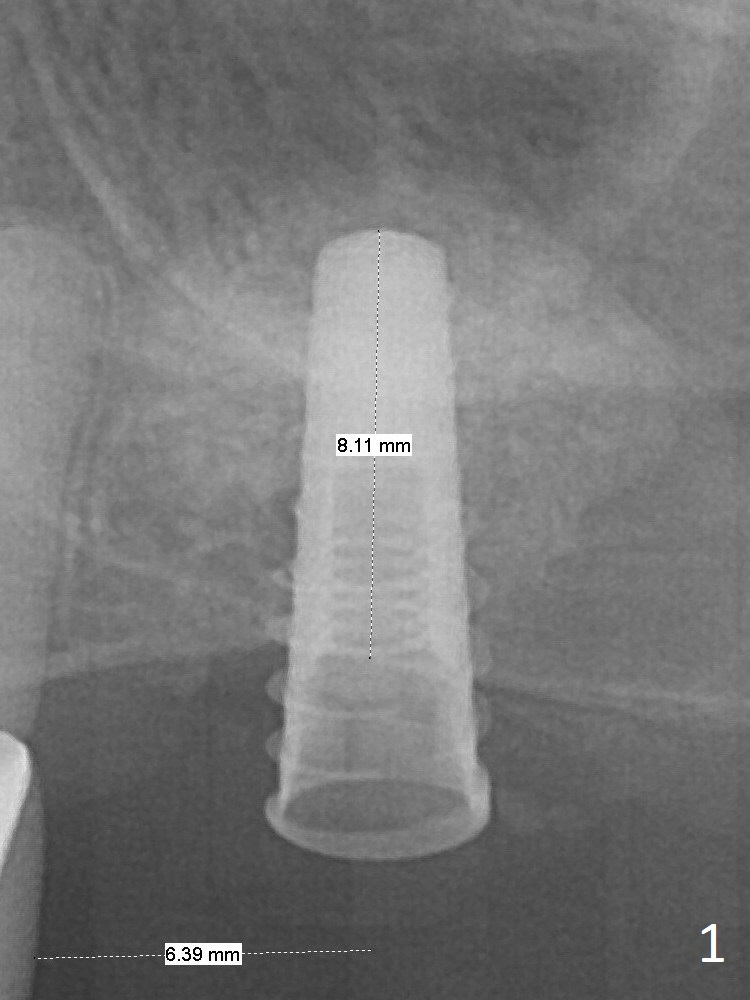

Magic Sinus Lifter is used to elevate the sinus floor for ~ 5 mm, followed by insertion of allograft/Osteogen and 4.0x11 mm dummy implant partially (Fig.1). With approximately 10% more of graft being placed, a 4.5x9 mm IBS implant is placed with insertion torque of 15 Ncm (Fig.2). The implant has a tenting effect. Fig.3 shows a coronal section of the sinus preoperatively.